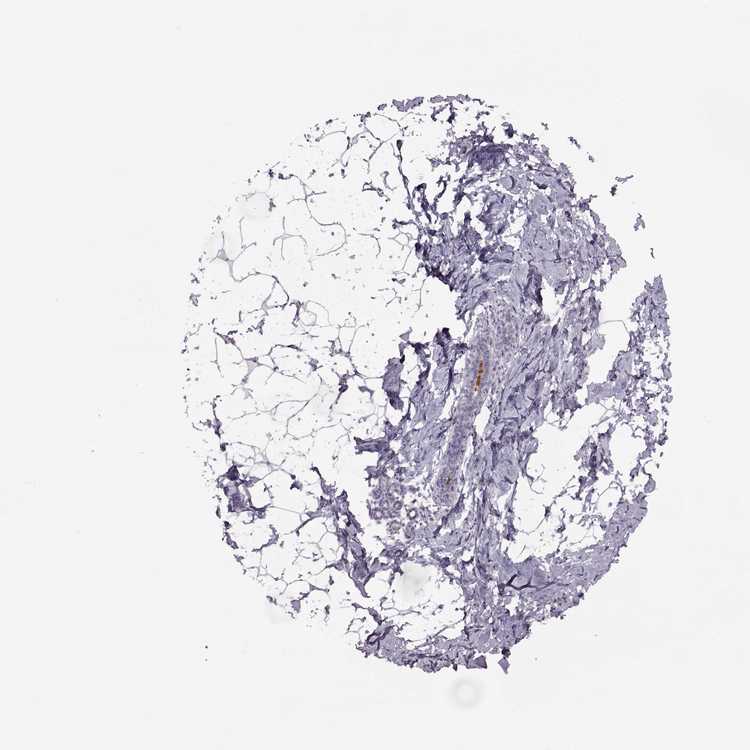

BREAST - Antibody stainingi

Antibody staining in the annotated cell types in the current human tissue is reported as not detected, low, medium, or high, based on conventional immunohistochemistry profiling in selected tissues. This score is based on the combination of the staining intensity and fraction of stained cells.

Each image is clickable and will lead to virtual microscopy that enables deeper exploration of all samples and also displays staining intensity scores, fraction scores and subcellular localization as well as patient and tissue information for each sample.

Antibody HPA003356

Adipocytes Not detected

Glandular cells Not detected

Myoepithelial cells Not detected